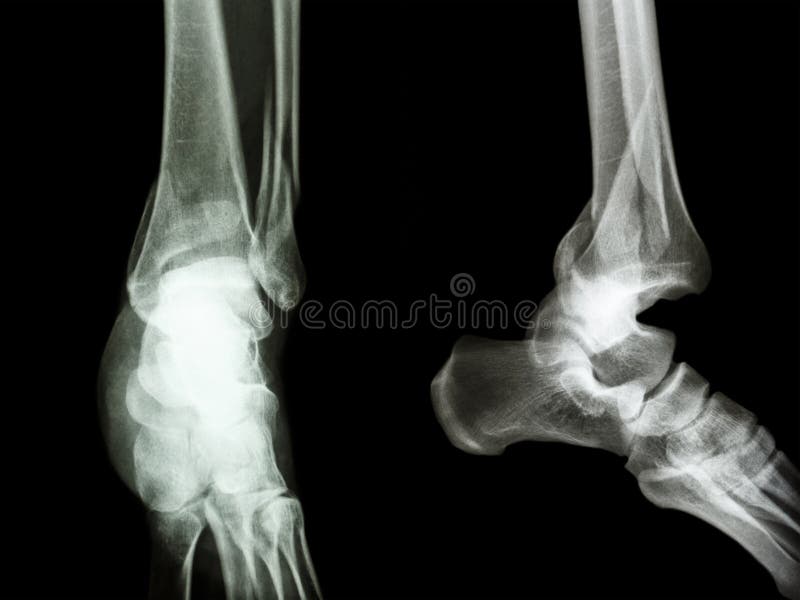

Caviglia E Piede Frattura Della Tibia

Le Fratture Della Caviglia

Frattura Della Caviglia I Sintomi Le Complicazioni E La Terapia Piu Rapida